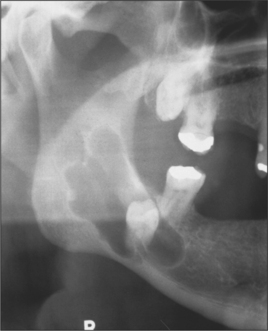

Site

Many cysts show a predilection for specific areas. For example, 75% of odontogenic keratocysts present at the mandibular angle (Fig. 9.3) whilst 88% of glandular odontogenic cysts occur at the anterior mandible (Cawson et al. 2001). Some cysts are completely site-specific such as the nasopalatine duct cyst, which arises from tissues within the incisive canal, and the paradental cyst, which is associated with impacted lower third molars. Also of note is the group of cysts that present in the gingival area including the inflammatory lateral periodontal cyst (a variant of a radicular cyst), the true lateral periodontal cyst, the peripheral odontogenic keratocyst and gingival cyst of adults. These classically present coronal to the apices and in-between teeth in the premolar areas.

Fig. 9.3 An odontogenic keratocyst at the angle of the mandible.

Lobulation

Where a radiolucency displays lobulation it is strongly suggestive of the keratocyst (Fig. 9.3), which has a pattern of cyst growth with ‘invasion’ of lining epithelium through the cancellous bone space leaving behind isthmi of bone.